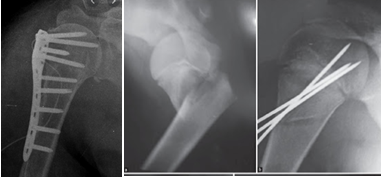

3. Điều trị phẫu thuật

* Chỉ định

- Gãy di lệch lớn, nắn chỉnh không đạt kết quả, đe doạ tổn thương mạch máu thần kinh.

- Gãy phức tạp, có mảnh rời.

- Gãy hở

- Gãy xương kết hợp với trật khớp vai.

* Phương pháp

- Kết xương nẹp vít:

- Xuyên đinh Kirschner